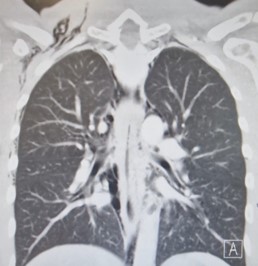

A chest X-ray performed (Figure 1) in the Emergency Department demonstrated significant subcutaneous emphysema. Subsequent computed tomography of the thorax showed extensive pneumomediastinum with a locule of intramural gas possibly reflecting a focal rupture point (Figure 2).

Figure 2: CT Thorax.